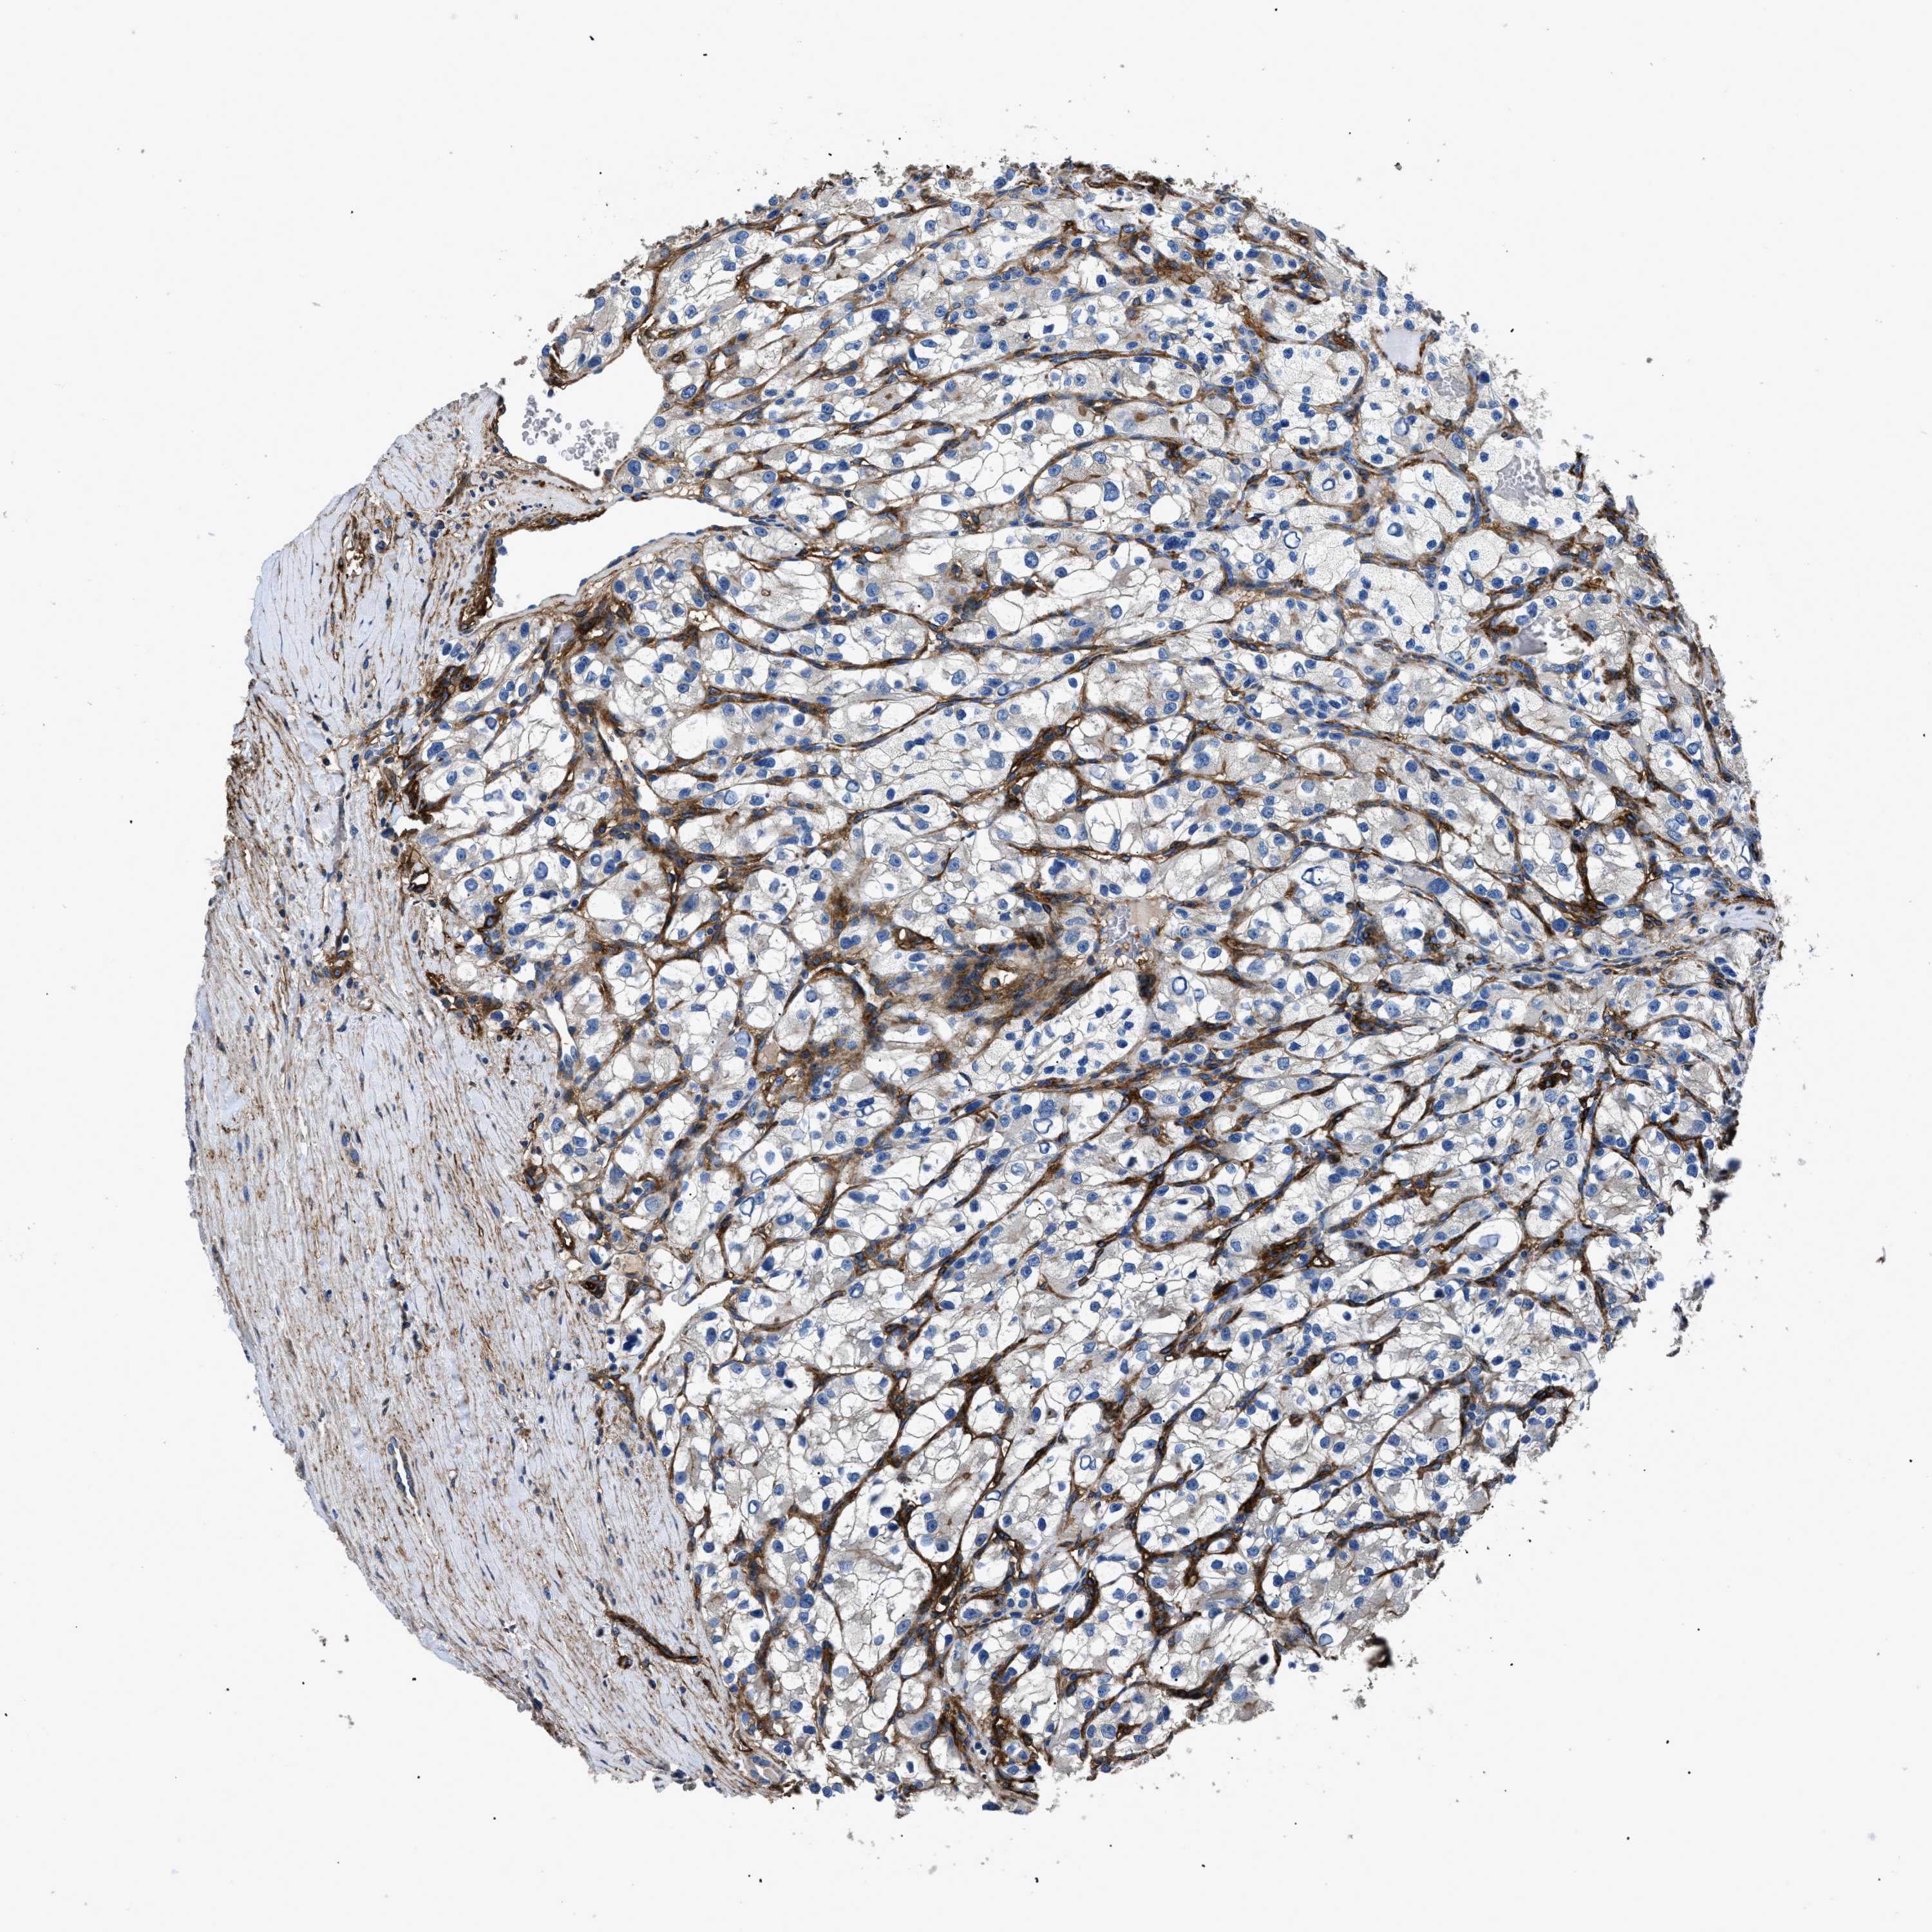

KIDNEY RENAL CLEAR CELL CARCINOMA (TCGA) - Interactive survival scatter ploti

The Survival Scatter plot shows the clinical status (i.e. dead or alive) for all individuals in the patient cohort, based on the same data that underlies the corresponding Kaplan-Meier plots. Patients that are alive at last time for follow-up are shown in blue and patients who have died during the study are shown in red.

The x-axis shows the expression levels (FPKM) of the investigated gene in the tumor tissue at the time of diagnosis. The y-axis shows the follow-up time after diagnosis (years). Both axes are complimented with kernel density curves demonstrating the data density over the axes. The top density plot shows the expression levels (FPKM) distribution among dead (red) and alive patients (blue). The right density plot shows the data density of the survived years of dead patients with high and low expression levels respectively, stratified using the cutoff indicated by the vertical dashed line through the Survival Scatter plot. This cutoff is automatically defined based on the FPKM cutoff that minimizes the p-score. The cutoff can be changed by dragging the vertical line or by entering a cutoff value in the square labeled "Current cut-off".

Under the Survival Scatter plot the p-score landscape (black curve; left axis) is shown together with dead median separation (red curve; right axis). Dead median separation is the difference in median mRNA expression between patients who have died with high and low expression, respectively. It is calculated as follows: median FPKM expression of dead patients with high expression - median FPKM expression of dead patients with low expression. This is intended to aid the user in visually exploring custom cutoffs and the associated p-scores and dead median separation.

Individual patient data is displayed and can be filtered by clicking on one or more of the category buttons on the top of the page. Categories describing expression level and patient information include: high, low, alive, dead, female, male and tumor stages. The scale of the x-axis can be toggled between linear and log-scale by clicking on the "x log" button. Mouse-over function shows TCGA ID, patient information and mRNA expression (FPKM) for each patient.

& Survival analysisi

Kaplan-Meier plots summarize results from analysis of correlation between mRNA expression level and patient survival. Patients were divided based on level of expression into one of the two groups "low" (under cut off) or "high" (over cut off). X-axis shows time for survival (years) and y-axis shows the probability of survival, where 1.0 corresponds to 100 percent.

CD276 is not prognostic in Kidney Renal Clear Cell Carcinoma (TCGA)

Best expression cut offi

Based on the FPKM value of each gene, patients were classified into two groups and association between prognosis (survival) and gene expression (FPKM) was examined. The best expression cut-off refers the FPKM value that yields maximal difference with regard to survival between the two groups at the lowest log-rank P-value. Best expression cut-off was selected based on survival analysis .

When clicking on this number, the vertical dashed line indicating cut-off, the interactive survival plot, and the Kaplan-Meier curve will be adjusted to show results based on the best expression cut-off.

: 16.38

P scorei

Log-rank P value for Kaplan-Meier plot showing results from analysis of correlation between mRNA expression level and patient survival.

N/A

TCGA RNA samplesi

RNA-seq data is reported as average FPKM (number Fragments Per Kilobase of exon per Million reads), generated by the The Cancer Genome Atlas (TCGA) .

Normal distribution across the dataset is visualized with box plots, shown as median and 25th and 75th percentiles. Points are displayed as outliers if they are above or below 1.5 times the interquartile range. FPKM values of the individual samples are presented next to the box plot.

Average pTPM 29.8

Number of samples 521